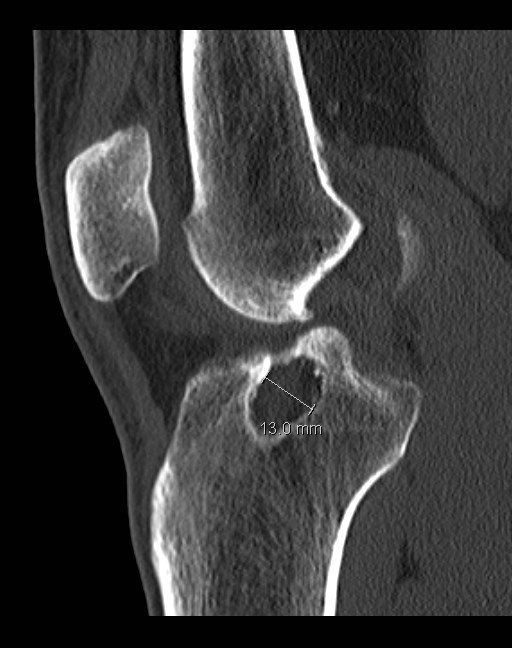

- CT scan:

- Pending on size and location of tunnels on X-rays, CT scan is often required

- This will help provide more detailed information on the size and position of the tunnels which is the key determinant whether revision ACL reconstruction can be performed in one sitting or two

- Tunnel dilation (see below)

- Tunnel dilation:

- The tunnels when they are drilled are cylindrical in nature

- Over time the tunnels may dilate and increase in diameter especially in between the apertures i.e. section between the entrance and exit of the bony tunnel in the femur and tibia

- If this dilation is >10-12mm in diameter then performing the operation in one sitting is more problematic as the tunnel will be bigger than the graft leading to problems with position, fixation and loosening:

- In this scenario (especially for tunnels much bigger than 10mm) it would be better to perform the revision in two stages: